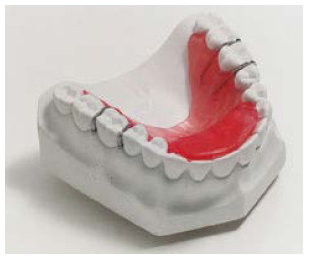

Other removable appliances: A bite plate (Figure 13) is an acrylic appliance that reduces a deep bite by preventing the posterior teeth from touching. A lip bumper (Figure 14) is a 0.036” size buccal wire that fits into the tubes on the mandibular molar bands. Pressure from the lips creates space along the dental arch. A splint is used for the treatment of TMD and facial pain. They may be designed for either arch depending on the treatment objectives. A tooth positioner (Figure 15) is worn after the braces are removed to achieve minor tooth movement and set the occlusion.

Figure 13. Bite plate.

Figure 13